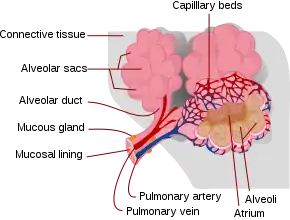

The physical processes behind pulmonary contusion are poorly understood. However, it is known that lung tissue can be crushed when the chest wall bends inward on impact.[25] Three other possible mechanisms have been suggested: the inertial effect, the spalling effect, and the implosion effect.

- In the inertial effect, the lighter alveolar tissue is sheared from the heavier hilar structures, an effect similar to diffuse axonal injury in head injury.[4] It results from the fact that different tissues have different densities, and therefore different rates of acceleration or deceleration.[8]

- In the spalling effect, lung tissue bursts or is sheared where a shock wave meets the lung tissue, at interfaces between gas and liquid.[19] The alveolar walls form such a gas-liquid interface with the air in the alveoli.[4][26] The spalling effect occurs in areas with large differences in density; particles of the denser tissue are spalled (thrown) into the less dense particles.[27]

- The implosion effect occurs when a pressure wave passes through a tissue containing bubbles of gas: the bubbles first implode, then rebound and expand beyond their original volume.[28] The air bubbles cause many tiny explosions, resulting in tissue damage;[28] the overexpansion of gas bubbles stretches and tears alveoli.[29][30] This effect is thought to occur microscopically when the pressure in the airways increases sharply.[25]

Pulmonary contusion results in bleeding and fluid leakage into lung tissue, which can become stiffened and lose its normal elasticity. The water content of the lung increases over the first 72 hours after injury, potentially leading to frank pulmonary edema in more serious cases.[19] As a result of these and other pathological processes, pulmonary contusion progresses over time and can cause hypoxia (insufficient oxygen).

Bleeding and swelling

In contusions, torn capillaries leak fluid into the tissues around them.[32] The membrane between alveoli and capillaries is torn; damage to this capillary–alveolar membrane and small blood vessels causes blood and fluids to leak into the alveoli and the interstitial space (the space surrounding cells) of the lung.[9] With more severe trauma, there is a greater amount of edema, bleeding, and tearing of the alveoli.[16] Pulmonary contusion is characterized by microhemorrhages (tiny bleeds) that occur when the alveoli are traumatically separated from airway structures and blood vessels.[23] Blood initially collects in the interstitial space, and then edema occurs by an hour or two after injury.[29] An area of bleeding in the contused lung is commonly surrounded by an area of edema.[23] In normal gas exchange, carbon dioxide diffuses across the endothelium of the capillaries, the interstitial space, and across the alveolar epithelium; oxygen diffuses in the other direction. Fluid accumulation interferes with gas exchange,[33] and can cause the alveoli to fill with proteins and collapse due to edema and bleeding.[23] The larger the area of the injury, the more severe respiratory compromise will be.[16]

Consolidation and collapse

Pulmonary contusion can cause parts of the lung to consolidate, alveoli to collapse, and atelectasis (partial or total lung collapse) to occur.[34] Consolidation occurs when the parts of the lung that are normally filled with air fill with material from the pathological condition, such as blood.[35] Over a period of hours after the injury, the alveoli in the injured area thicken and may become consolidated.[23] A decrease in the amount of surfactant produced also contributes to the collapse and consolidation of alveoli;[15] inactivation of surfactant increases their surface tension.[30] Reduced production of surfactant can also occur in surrounding tissue that was not originally injured.[25]